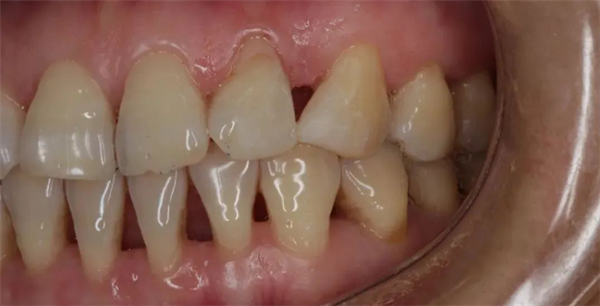

刚开始,仅仅是出现牙龈红肿及出血,并不一定导致疼痛,图源:作者提供 刚开始,仅仅是出现牙龈红肿及出血,并不一定导致疼痛,图源:作者提供 慢慢地,你不在意,牙龈只是有点退缩,然后牙齿缝慢慢显露出来,露出难看的黑三角。

由于牙龈退缩,牙齿之间形成了黑三角,此时要治疗和改善已经非常困难,图源:作者提供 由于牙龈退缩,牙齿之间形成了黑三角,此时要治疗和改善已经非常困难,图源:作者提供 再后来(可能又过了好多年、数十年),你可能突然会觉得有几颗牙齿有点松动、嚼东西已经没那么有力了,时不时还有咸咸涩涩的脓液流出来。——这时候,有的人可能会出现疼痛,但也有的不会。

速读:跟蛀牙、牙髓炎这些病情发展会导致牙齿疼痛的病不一样,更多的时候,牙周炎的发展开始的时候非常非常缓慢,就像温水煮青蛙,没有特别明显的急性症状,这也是很多年轻人在疾病刚刚开始的时候并不在意的原因。 大量牙结石,导致牙齿松动移位,图源:作者提供。 而之前松动的牙齿开始摇摇晃晃,有的还会出现牙齿的疼痛! 由于牙龈退缩,牙齿之间形成了黑三角,此时要治疗和改善已经非常困难,图源:作者提供。 另外,药物在牙周炎治疗中的作用,经常不是吃的——漱口是常见的药物使用方法,另外一种则是把药物塞在牙齿周围的沟里,局部发挥抗菌作用。